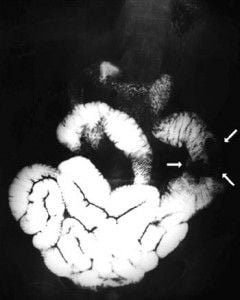

Abdomen, aparato digestivo y via biliarTécnicas de Exploración Radiológica Tránsito del intestino delgado Parte II 28 junio, 2012 Tidito Transito intestinal contraste simple Transito intestinal doble contraste yeyuno e ileon Patologia de Transito intestinal – Enfermedad celiaca Tumor maligno ileon terminalEnfermedad inflamatoria intestinal